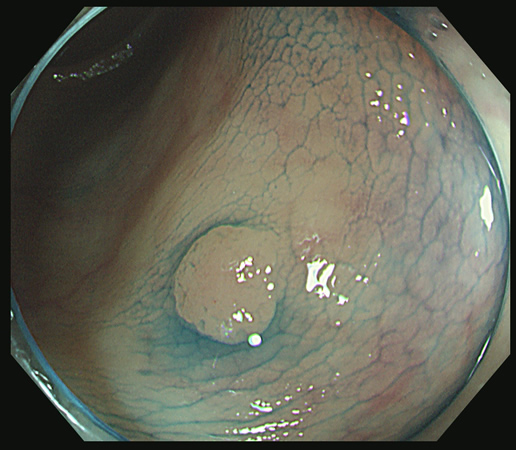

前項で述べましたように「不完全切除」は良く起こる現象で、しばしば「内視鏡後・大腸癌」の原因になります

「Extended Cold法」で切除し、切除創を詳細に観察することが肝要です

「遺残の可能性」がわずかでもある場合は、「辺縁のトリミング」を追加します